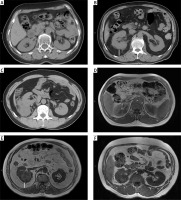

The MAPS was computed by 2 measurements as follows: the thickness of the posterior renal fat and the extent of the perirenal fat stranding around the renal tumour at the level of the renal vein on CT scan or T1 MRI scan (Photo 1). The thickness of the posterior renal fat was calculated as the distance between the posterior renal capsule and the body in centimetres (< 1 cm = 0 points; 1.0–1.9 = 1 points; ≥ 2.0 cm = 2 points). A perirenal fat stranding extent score was acquired at one level (no stranding = 0 points, mild stranding = 2 points, severe stranding = 3 points). The total score (0–5 points) was obtained by adding the 2 scores together [9].

Photo 1

Mayo Adhesive Probability (MAP) score calculation-the thickness of the posterior renal fat (white line on the image) and grading of perinephric stranding on CT and MRI. A, D – No stranding: 0 points. The perirenal adipose tissue shows no stranding on (A) CT and (D) MRI. B, E – MAP score: 4 points. The thickness of the posterior renal fat is 2.4 cm (2 points) with moderate stranding (2 points) on (B) CT, and the posterior distance is 2.6 cm (2 points) with moderate stranding (2 points) on (E) MRI. C, F – Severe stranding: 3 points. The perirenal adipose tissue shows severe stranding with thick image-dense bars of inflammation on (C) CT and (F) MRI

CT – computed tomography, MRI – magnetic resonance imaging.